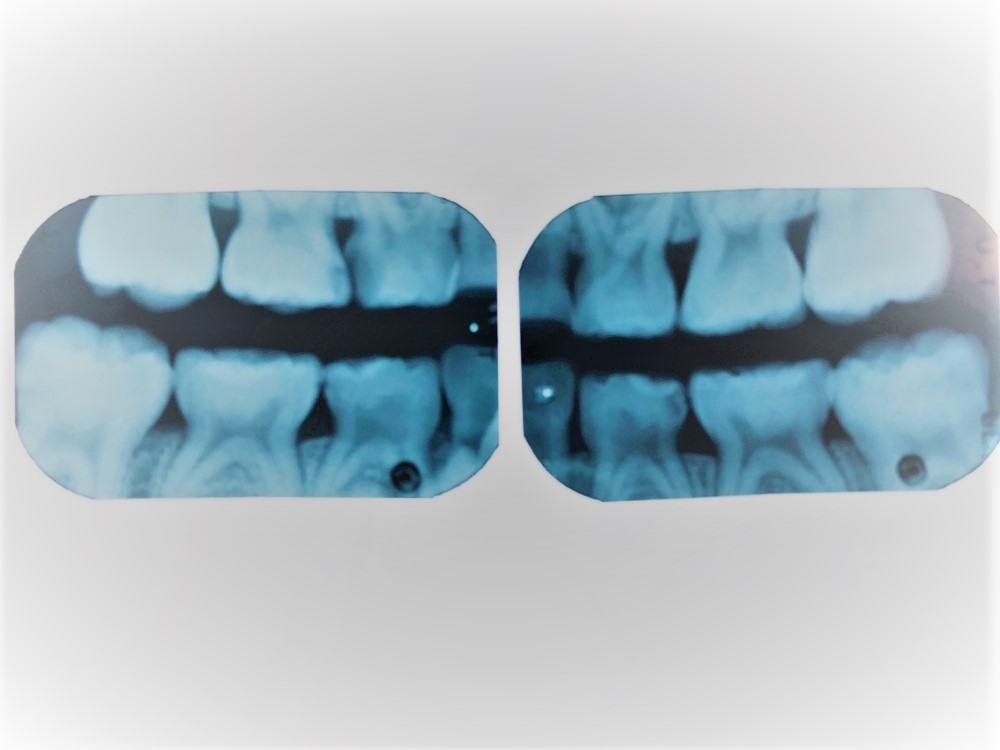

目視では確認できない虫歯も見つけられるレントゲン撮影(バイトウィング法)を導入し、精度の高い診療につなげています。